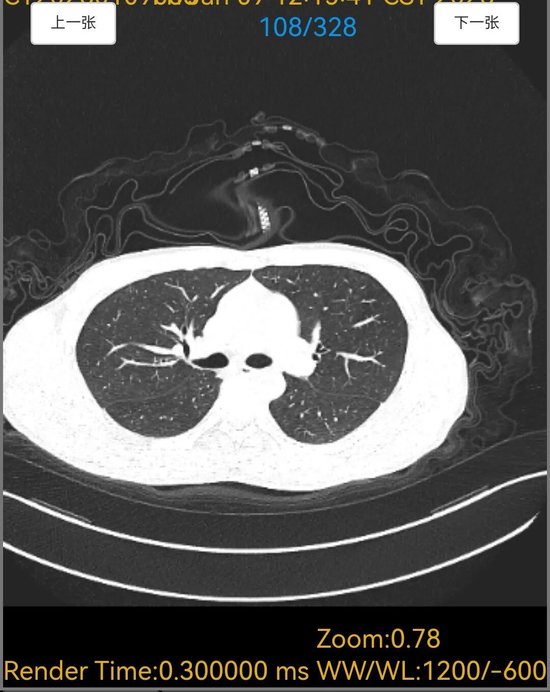

6天胸闷气短、5天持续高热,18岁的小宋被紧急送入平原县人民医院呼吸内科,胸部CT检查结果让接诊医生忧心不已,双肺布满大片“毛玻璃”阴影,呈现弥漫性病变,提示肺部正遭受严重侵袭。更棘手的是,常规感染筛查中,细菌、病毒等常见病原体检测均为阴性,病因成谜,治疗陷入困境。

诊断明确后,呼吸内科医师团队制定了针对性极强的精准治疗方案。令人惊叹的疗效随之出现,在针对性药物治疗仅5天后,患者复查胸部CT。影像对比显示,原本遍布双肺的弥漫性“毛玻璃”阴影已基本完全吸收